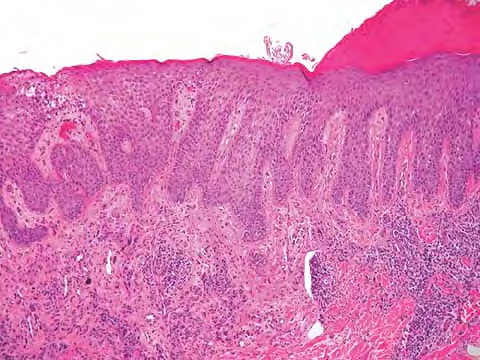

Read Moremetastasis OLYMPUS DIGITAL CAMERA OLYMPUS DIGITAL CAMERA OLYMPUS DIGITAL CAMERA OLYMPUS DIGITAL CAMERA OLYMPUS DIGITAL CAMERA OLYMPUS DIGITAL CAMERA